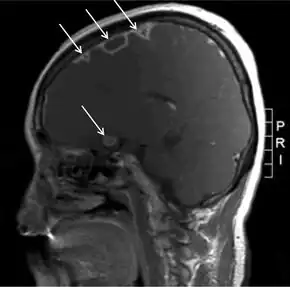

MRI showing multiple epidural and brain abscesses due to Lemierre syndrome

During the primary infection, F. necrophorum colonizes the infection site and the infection spreads to the parapharyngeal space. The bacteria then invade the peritonsillar blood vessels where they can spread to the internal jugular vein.[6] In this vein, the bacteria cause the formation of a thrombus containing these bacteria. Furthermore, the internal jugular vein becomes inflamed. This septic thrombophlebitis can give rise to septic microemboli[12] that disseminate to other parts of the body where they can form abscesses and septic infarctions. The first capillaries that the emboli encounter where they can nestle themselves are the pulmonary capillaries. As a consequence, the most frequently involved site of septic metastases are the lungs, followed by the joints (knee, hip, sternoclavicular joint, shoulder and elbow[13]). In the lungs, the bacteria cause abscesses, nodulary and cavitary lesions. Pleural effusion is often present.[7] Other sites involved in septic metastasis and abscess formation are the muscles and soft tissues, liver, spleen, kidneys and nervous system (intracranial abscesses, meningitis).[6]